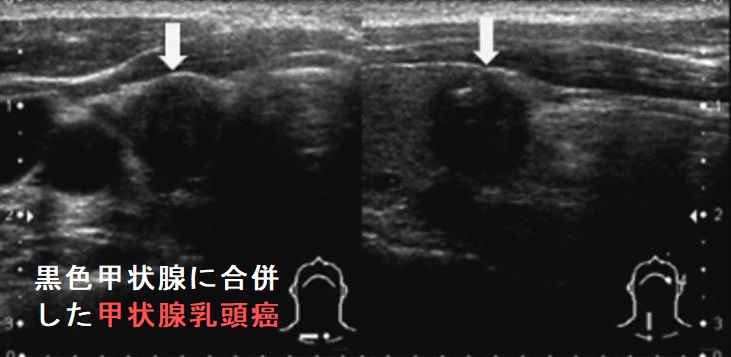

- 黒色甲状腺

黒色甲状腺は無害との報告が多いですが、

- 薬剤性甲状腺炎(無痛性甲状腺炎)も誘発します[Thyroid. 2008 Jul;18(7):795-7.][Horm Res Paediatr. 2019;92(4):276-283.]

- 甲状腺機能低下症を引きおこす可能性もあります[Int J Legal Med. 2006 May;120(3):157-9.][J Pediatr. 2016 Jun;173:232-4.]

黒色甲状腺は、ミノサイクリン非投与例に見られる事もあります。